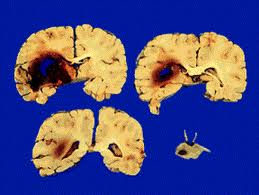

Внутримозговое кровоизлияние относят к острым нарушениям мозгового кровообращения (ОНМК) по геморрагическому типу. Любые внутримозговые кровоизлияния обычно развиваются остро, с непрерывным нарастанием симптоматики в течение нескольких минут или часов.

Причины кровоизлияния: В 70-80% случаев спонтанное кровоизлияние в мозг это следствие артериальной гипертензии; более редкие причины: аневризмы и мальформации, опухоли мозга, антикоагулянтная терапия, тромбозы мозговых вен и венозных синусов, септические эмболии, мигрень, кровоизлияние при физическом напряжении, при жировой эмболии, кровоизлияние при острой интенсивной боли и др.

По причине развития заболевания различают: первичные кровоизлияния в мозг (связаны чаще всего с артериальной гипертензией); вторичные кровоизлияния в мозг (связано с патологией сосудов: аневризмы, мальформации, васкулиты и др.);